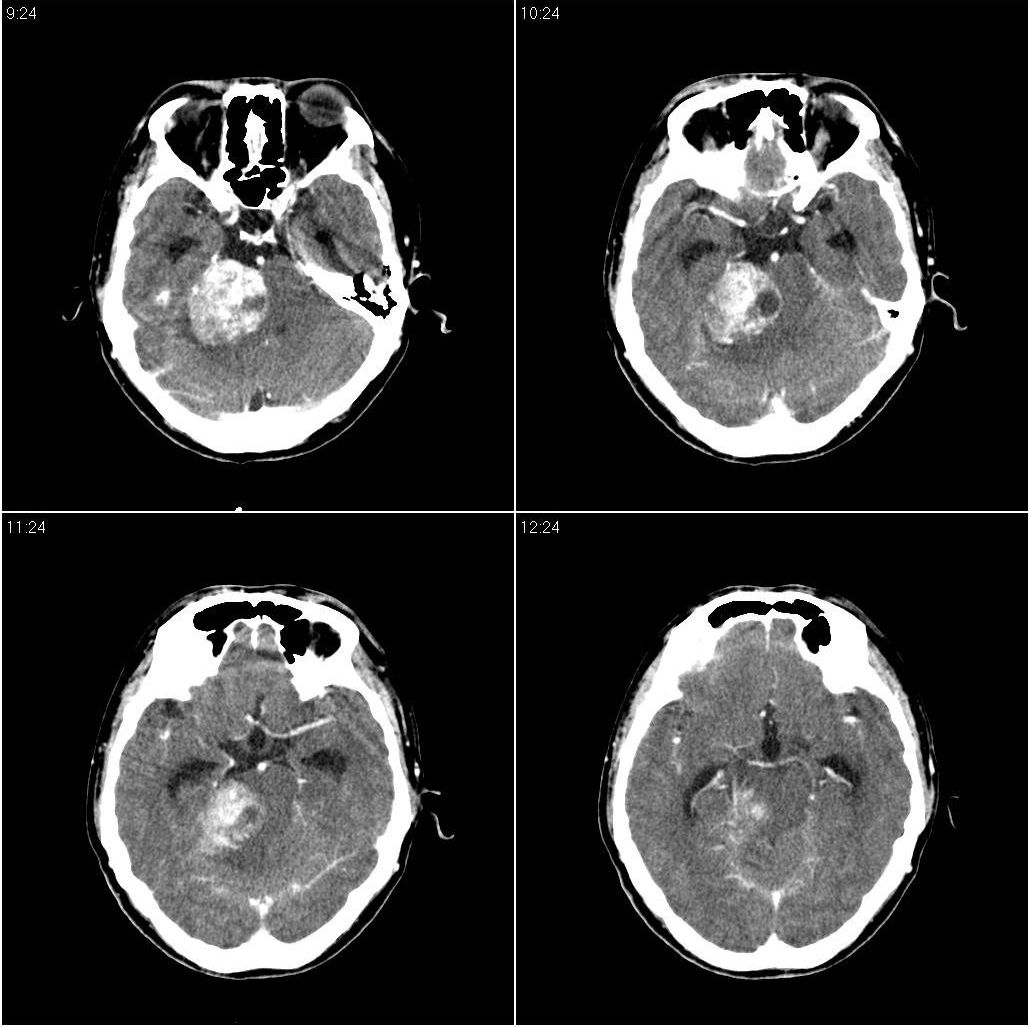

看到骨窗了,右侧内听道扩大(再往下扫一层),支持听神经瘤

现在有骨窗了,内听道口好像被开挖了一样,支持考虑听神经瘤先

支持幕下占位,右侧内听道扩大,听神经瘤可能,建议核磁

右侧桥小脑角区占位性病变,内听道扩大,骨质似见破坏,考虑为听神经瘤

右侧内听道扩大,支持听神经瘤

1)右侧听神经瘤。2)脑积水(梗阻性)。3)空蝶鞍。